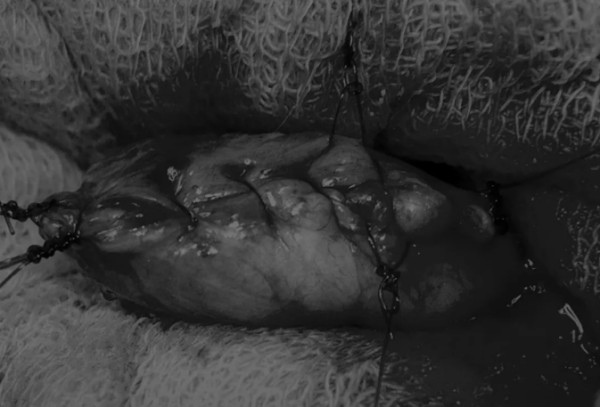

手术方法 在中线开腹手术后,确定膀胱,将其取出并隔离(图1)。为了使膀胱持续暴露,可在膀胱中线两侧各放置一根固定缝线(图2)。 在切开膀胱前,应用膀胱穿刺的方法获取尿液样本进行微生物培养。 图2 在手术过程中,还需要另外两根固定缝线来保持膀胱切开术的膀胱边缘处于暴露状态 在牵引缝线之间选择血管扩张较差的区域用手术刀切开膀胱壁(图3)。在牵引缝合线之间用手术刀在血管不良的区域做切口。切开膀胱壁后,膀胱内的手术可按手术方案实施,例如取出结石(图4)。 图3 避开主要的膀胱血管,做一个尽可能小的切口 切口可以在膀胱背侧或腹侧进行,避免对大血管的损伤。 图4 这张图显示了从膀胱中取出的大量结石 完成膀胱内冲洗后,应通过导尿管反向冲洗膀胱;砂样结石和血块会被冲到切口表面(图5) 图5 通过导尿管注入无菌生理盐水反向冲洗,可以去除微小的结石(箭头)和夹杂在膀胱黏膜皱褶中的砂样结石,以及可能在手术中形成的血块 膀胱创面采用单丝合成可吸收缝线缝合,采用外科医生习惯的缝合方式,但注意不要刺穿黏膜层(图6、图7)。 图6 使用简单的连续缝合。尽量不要用针刺穿黏膜层(箭头),以免缝线与尿液接触 图7 缝线应带入足够的切口两侧的膀胱组织,以确保在膀胱充盈时,没有伤口裂开 图8 这张图显示了通过导尿管注射的盐水,在缝合的切口处没有液体渗漏 关膀胱后,将无菌盐水注入膀胱腔内,检查是否有渗漏(图8)。 膀胱切开术闭合创口后,冲洗腹腔,以清除可能进入腹腔中的任何尿液、沙样结石或血凝块。 然后膀胱上覆盖小片的网膜,开腹手术伤口以通常的方式闭合。 手术视频 长按识别二维码观看视频